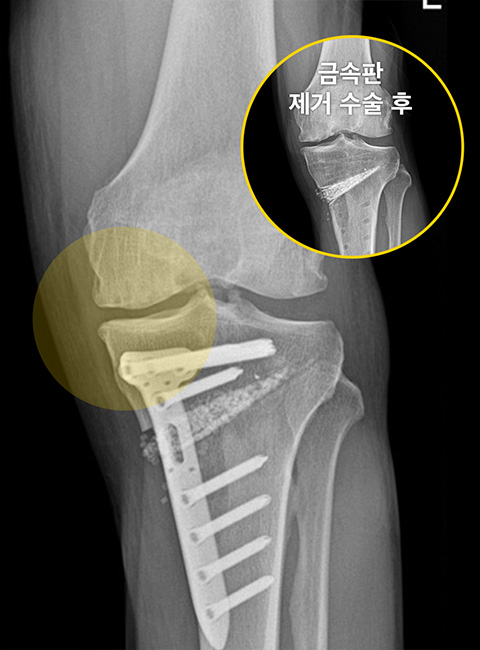

Before

무릎 안쪽 연골 간격이 좁아져 통증을 유발하는 상태

-

After

하중을 무릎 바깥쪽으로 분산시켜 좁아져 있던 무릎 안쪽 간격이 넓어짐 (금속판 제거 후 삽입한 인공뼈도 완전히 유합된 상태)